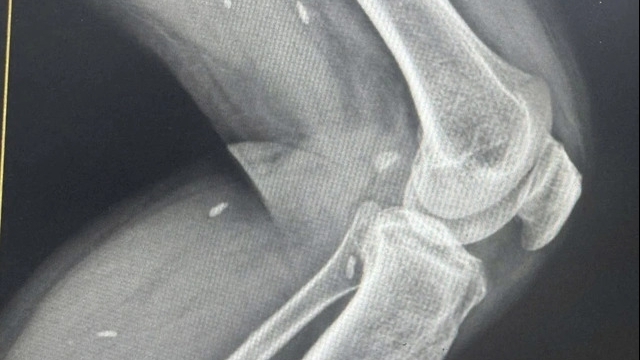

Theo đó, bé P. nhập viện vào ngày 19/1 với những biểu hiện sốt cao, viêm tấy bàn chân và đùi trái. Bệnh nhân được các bác sỹ xác định bị nhiễm khuẩn Burkholderia pseudomalei (hay còn gọi là khuẩn ăn thịt người) gây nên.

Bác sỹ Phạm Thị Ngọc Hân, Trưởng khoa Nhi, Bệnh viện hữu nghị Việt Nam - Cuba Đồng Hới cho biết: Sau chỉ 1 ngày nhập viện, tình trạng viêm tấy lan ra rất nhiều nơi trong cơ thể, sau đó tạo thành các ổ áp xe, nếu không điều trị kịp thời có thể nguy hiểm đến tính mạng.

Các bác sĩ khẳng định những vết mổ của gà vào cơ thể bệnh nhân đã vô tình giúp vi khuẩn Burkholderia pseudomalei xâm nhập. Nếu không phát hiện sớm và điều trị kịp thời, bệnh sẽ gây ra biến chứng khôn lường, như: nhiễm khuẩn huyết, sốc nhiễm khuẩn, tổn thương phổi, phải cắt bỏ tứ chi… thậm chí có thể dẫn đến tử vong.